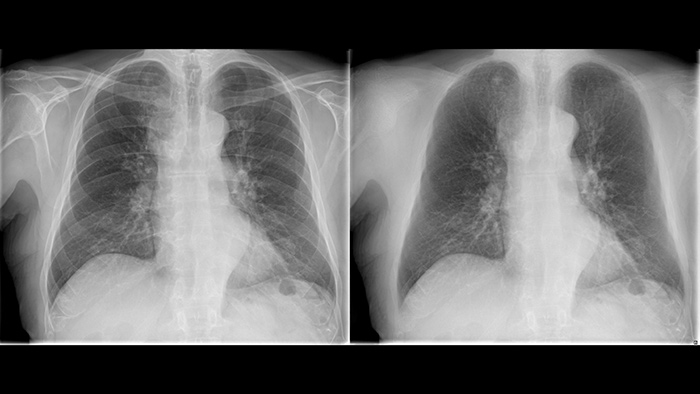

Next generation image processing with Philips UNIQUE 2

Philips Bone Suppressionimproves actionable lung nodule detection up to 16.8%4

Philips UNIQUE 2 improves image quality with more homogeneous black backgrounds, reduced noise and automatic enhancement of small details

Philips Bone Suppression3 helps remove bone structures from chest images for an unobstructed view of soft tissue and can improve actionable nodule detection by up to 16.8% without the need to expose the patient to additional X-ray dose.4